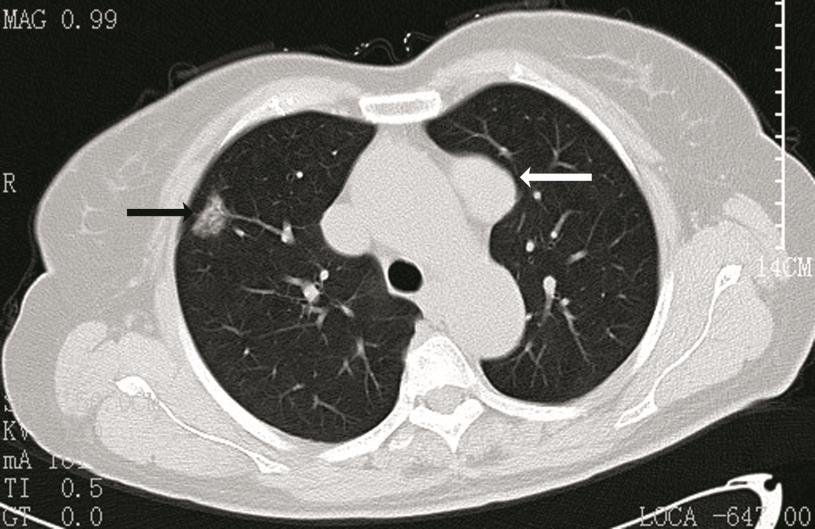

Lung scarring is also a strong possibility. When CT scans were taken of former COVID-19 patients, there were visible patches of unrepaired tissue, named "ground-glass opacities," as per Vox News. A study in China found that these glass opacities were found in a whopping 77% of COVID-19 patients. COVID-19 affects both lungs, unlike other respiratory epidemics of the past (SARS, MERS), escalating the risk of long-term scarring.

Above is a CT-scan of a chest showing a ground-glass opacity in the right superior lobe (black arrow). Image is courtesy of Research Gate.